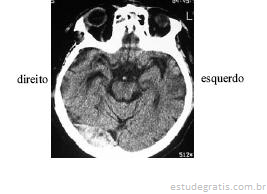

Após ter sofrido queda de um cavalo, um senhor de 55 anos de idade foi levado imediatamente ao pronto-socorro, onde se verificou, além das escoriações no corpo, pequeno hematoma subgaleal em região temporoparietoccipital direita. Foi medicado com analgésicos e antiemético. Após vinte minutos, os sintomas foram aliviados e o paciente solicitou alta hospitalar. O clínico geral solicitou o parecer do neurologista visto que os socorristas relataram perda de consciência, fato negado pelo paciente. Passadas 4 horas do trauma, o paciente mostravase inquieto, mas negava cefaléia ou náuseas. Foi levado para realização de tomografia computadorizada, cujo resultado é mostrado na figura acima. Na presença do neurologista, o paciente solicitou alta hospitalar, informando que morava a apenas 25 km do hospital e voltaria se houvesse piora. Diante de situação como a apresentada, após analisar o exame de imagem e o caso clínico, o neurologista deve